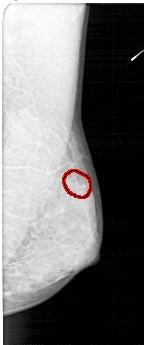

A_1352_1.LEFT_CC

LEFT_CC LINES 4711 PIXELS_PER_LINE 2236 BITS_PER_PIXEL 12 RESOLUTION 43.5 NON_OVERLAY

FILE: A_1352_1.RIGHT_CC.OVERLAY

TOTAL_ABNORMALITIES 1

ABNORMALITY 1

LESION_TYPE CALCIFICATION TYPE PLEOMORPHIC DISTRIBUTION CLUSTERED

ASSESSMENT 4

SUBTLETY 2

PATHOLOGY BENIGN

TOTAL_OUTLINES 1

BOUNDARY